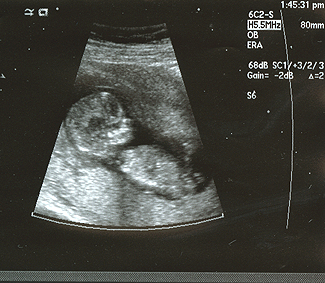

Hello lovely TTGP-ers! I've made it to 12 weeks and had my NT scan yesterday. I won't get the bloodwork results back for a while, but the doctor said the nuchal fold was very thin (good sign) and everything looked great. Phew! It was absolutely amazing to see the baby kicking her/his legs and swinging his/her arms around. And what a sweet lil' profile!